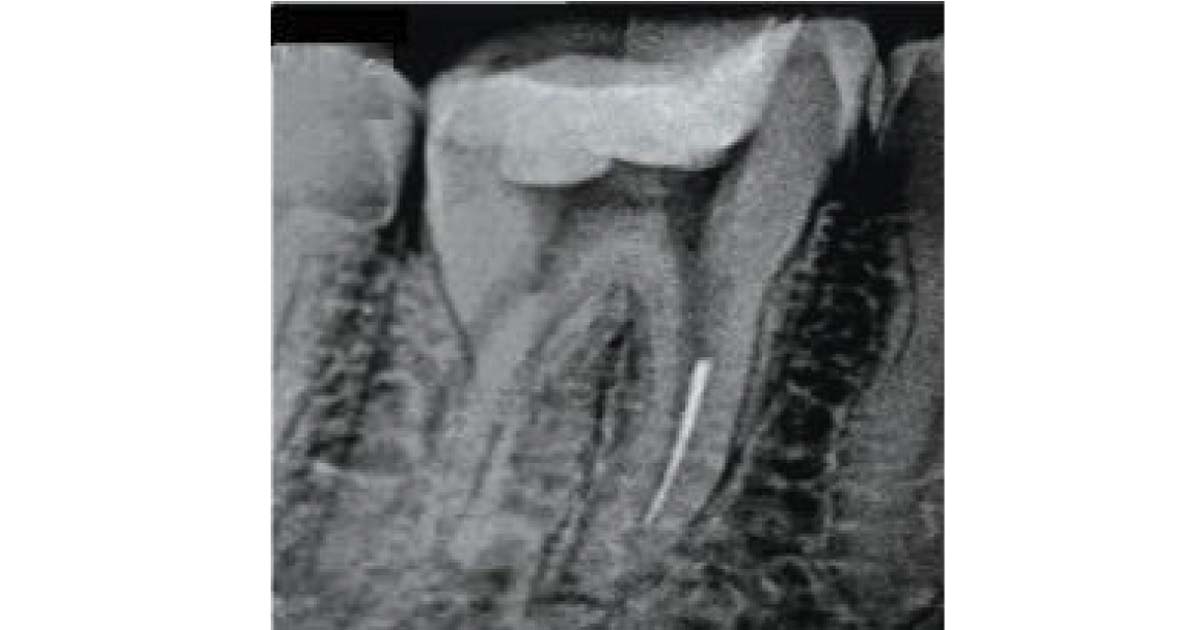

3. Separation of instruments:

Instrument separation usually happens when an instrument is forced into the dentinal structure or overused. Fracturing of an instrument in the apical third is often difficult to bypass, whereas in the coronal third, it can usually be removed or negotiated to the apex. Prognosis and management depend on the separation level, instrument size, infection severity, operator skill, patient motivation, and planned treatment. Many instrument retrieval kits are available on the market today, widely used by endodontists. These kits can be conveniently explored on our website, DentalKart.